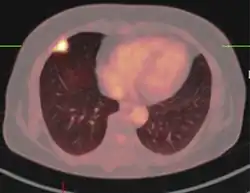

If there is an intermediate risk of malignancy, further imaging with positron emission tomography (PET scan) is appropriate (if available). It can be done simultaneously as a CT scan in the form of PET-CT. Around 95% of patients with a malignant nodule will have an abnormal PET scan, while around 78% of patients with a benign nodule will look normal on PET (this is the test sensitivity and specificity).[15] Thus, an abnormal PET scan will reliably pick up cancer, but several other types of nodules (inflammatory or infectious, for example) will also show up on a PET scan. If the nodule has a diameter of less than one centimeter, PET scans are often avoided because of an increased risk of falsely normal results.[15][16][17] Cancerous lesions usually have a high metabolism on PET, as demonstrated by their high uptake of FDG (a radioactive sugar).

-

PET-CT of a tuberculoma.